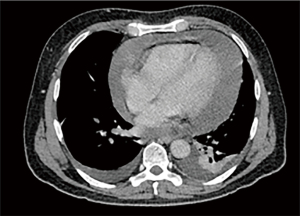

The pulmonary angiography revealed a right lobar/segmental PE (Figure 1) and a significant pericardial effusion (Figure 2) measuring 40 mm with a density of 15 HU. The patient was then admitted to the cardiology department for additional diagnostic evaluation. MSCT of the chest indicated enlarged paratracheal and subcarinal lymph nodes (Figure 3A,3B), while the MSCT of the abdomen showed no abnormalities. A transapical approach was utilized for the pericardiocentesis, during which 2.5 liters of hemorrhagic fluid were extracted and sent for cytological, microbiological, and biochemical examination. The subsequent results confirmed the type of exudative effusion, and the cytological examination indicated that there was intense and atypical growth of mesothelial cells. Thoracocentesis was subsequently performed and the analysis that followed corroborated the earlier findings. Due to suspicion of a systemic autoimmune disease or antiphospholipid syndrome, which could explain multisystem serositis (pleural and pericardial involvement), elevated inflammatory markers, thromboembolic event (PE), lymphadenopathy and constitutional symptoms, immunological tests were indicated.